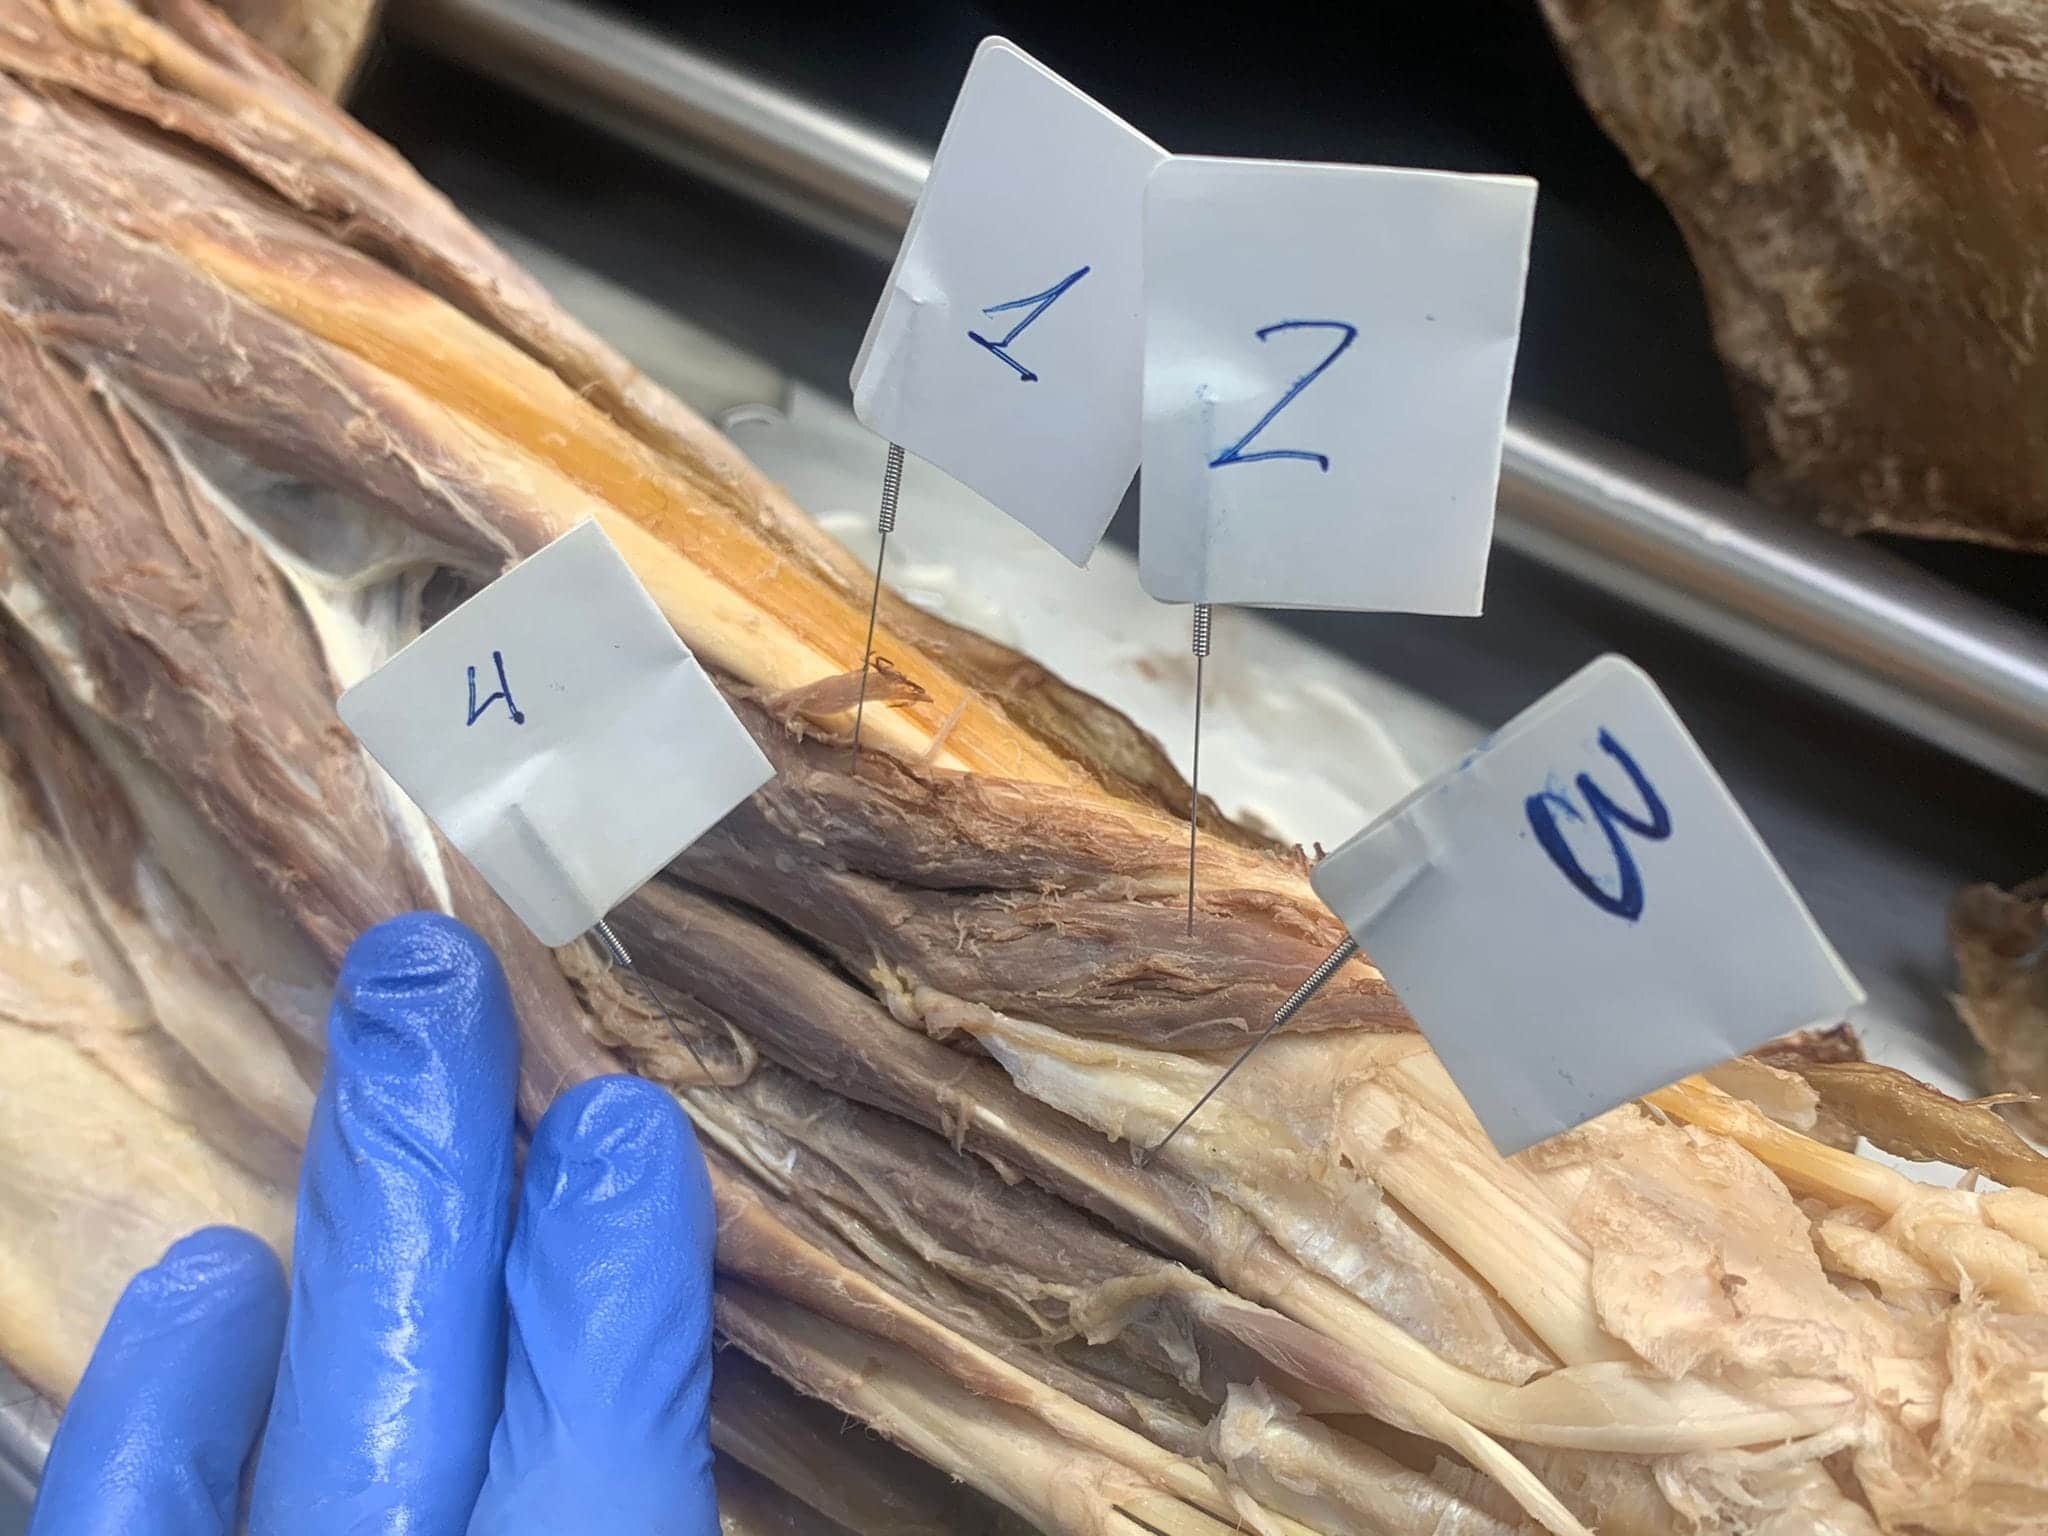

LUGAR: Av. de los Jerónimos, 135, 30107 Guadalupe (Murcia) – Sala de disección de la UCAM (Aulario 6)

DURACIÓN: 20 Horas

DOCENTES: Antonio García Godino, Manuel Moreno Más, Jose María Belmonte Hernández y Andrés Martínez Almagro

DIRIGIDO A: Fisioterapeutas y alumnos de fisioterapia